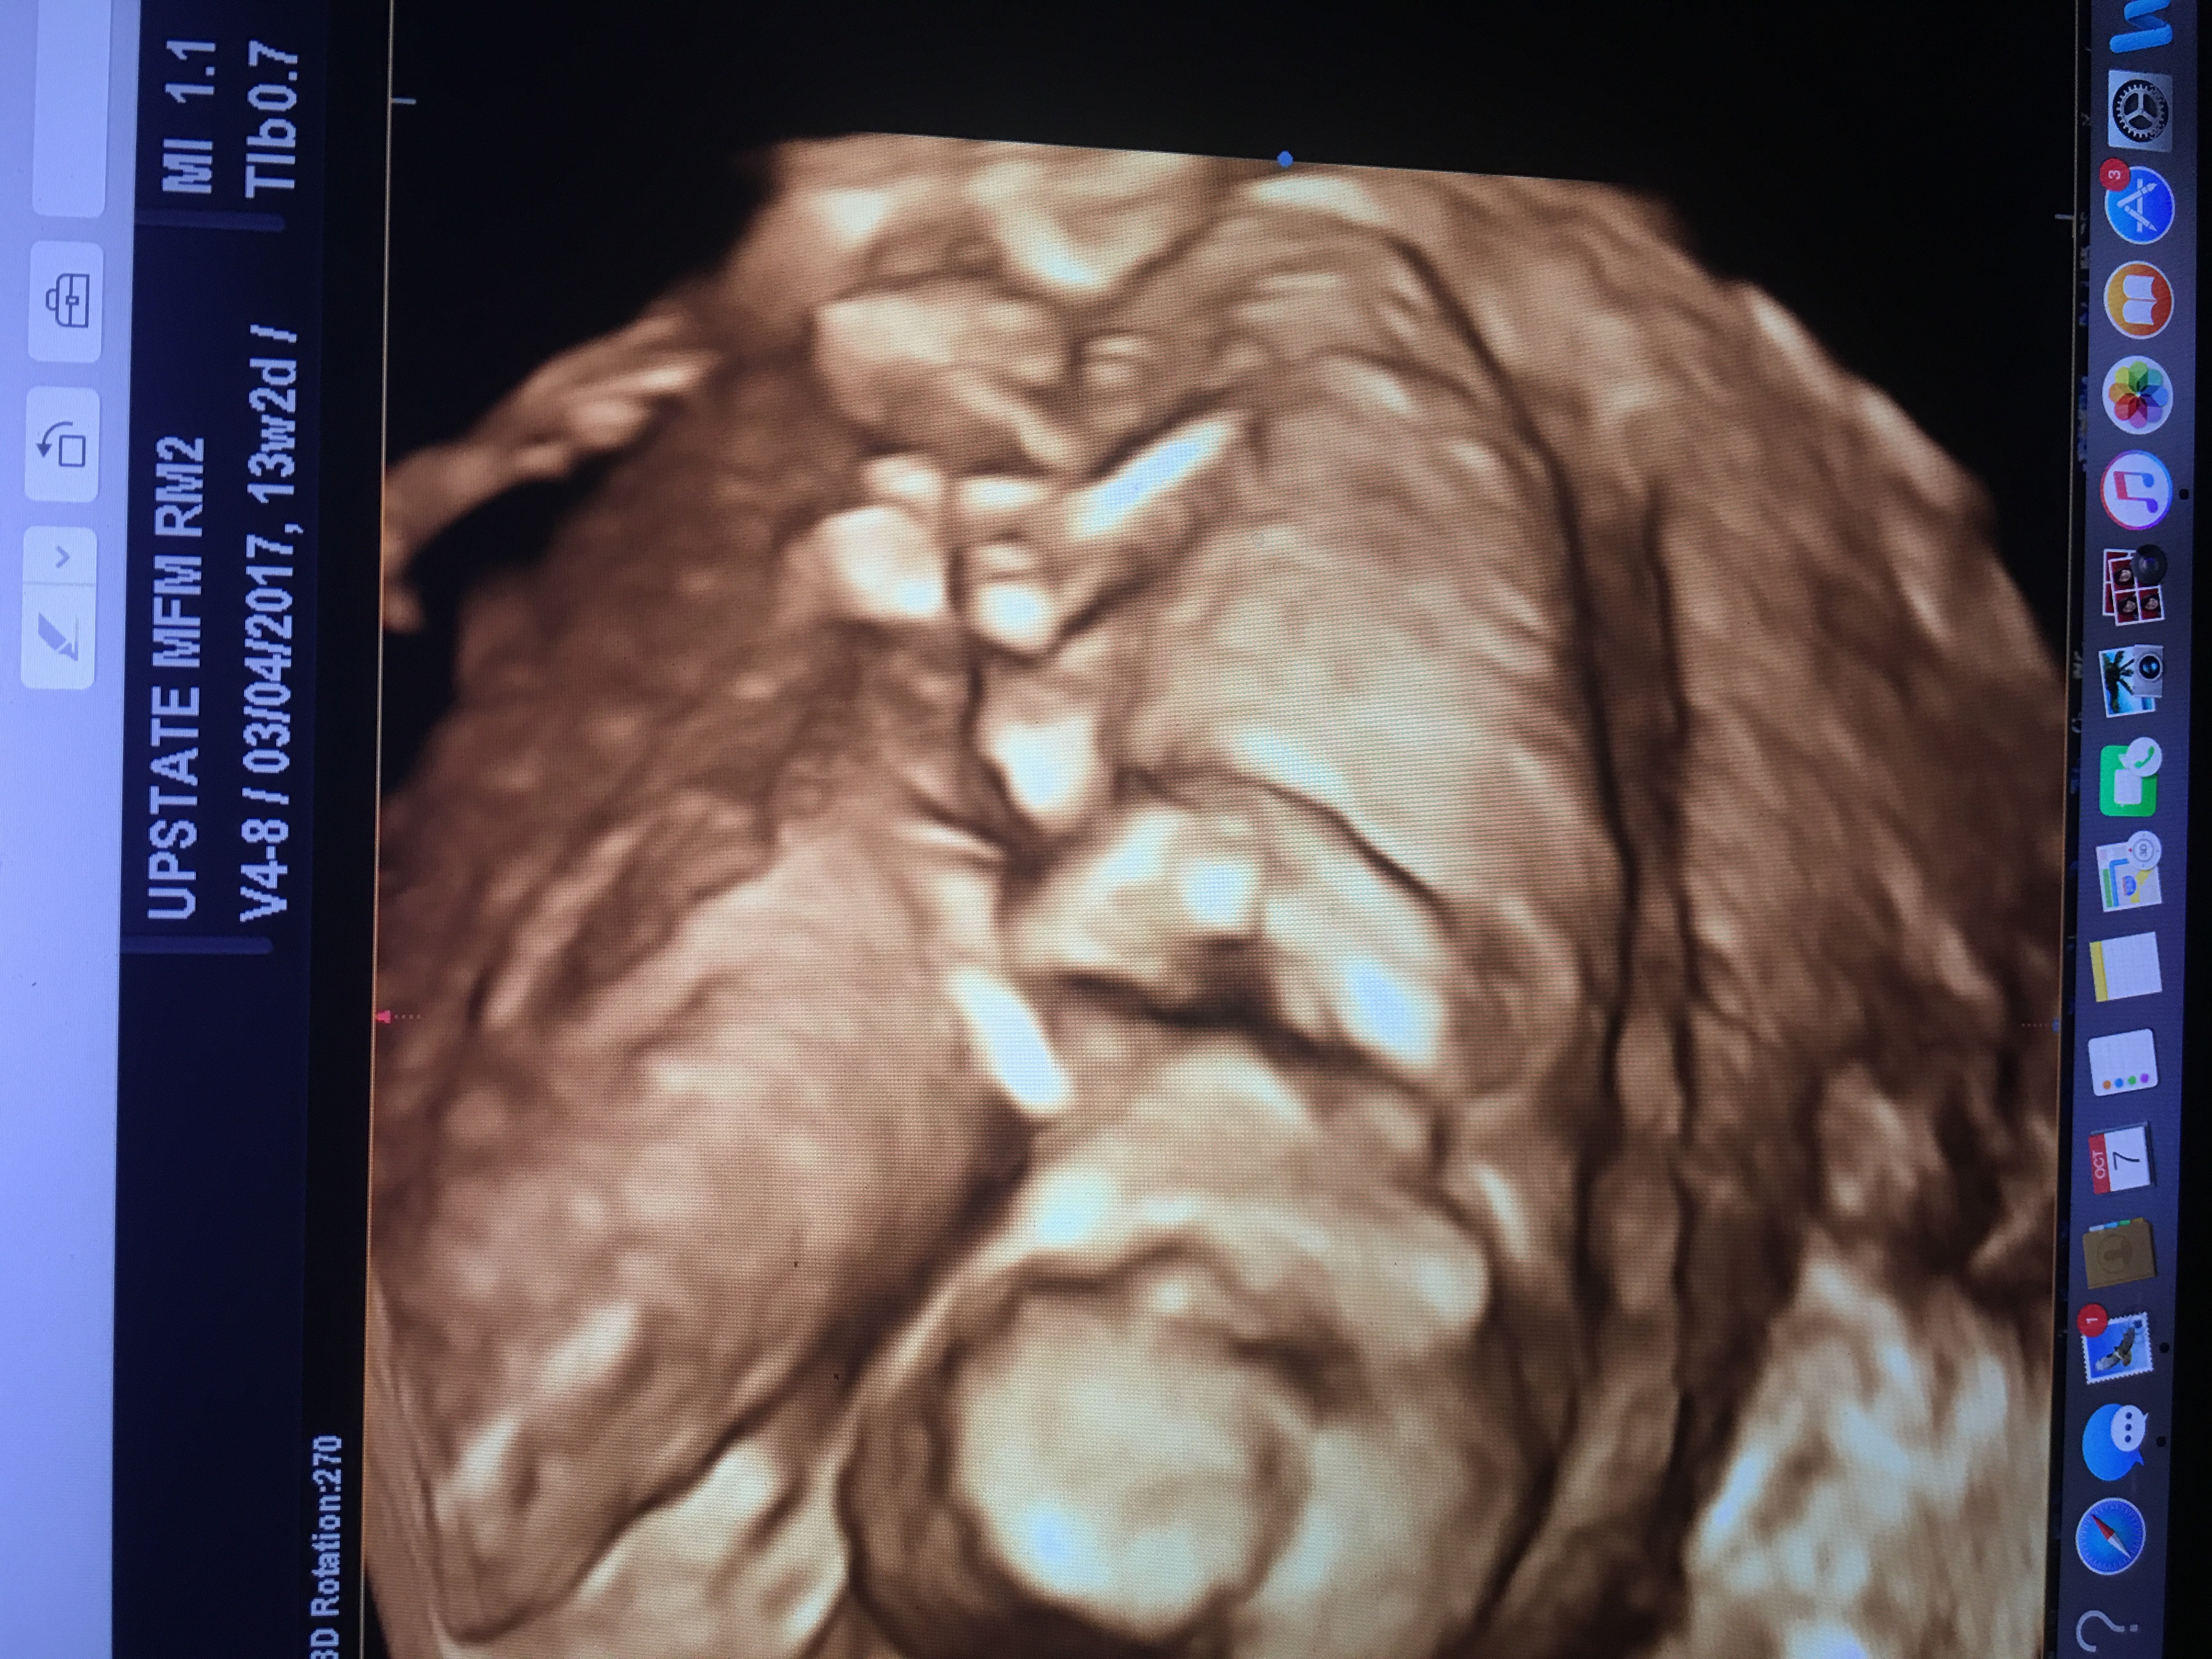

Attachment 35008

Maybe boy. Any 2D pics?

We didn't want to find out the sex so the only other pics are of face in 2d. These were the only full body ones we got. Just curious if anyone had any good guesses :)

It looks to me like a boy nub sticking out there, so I guess boy :)